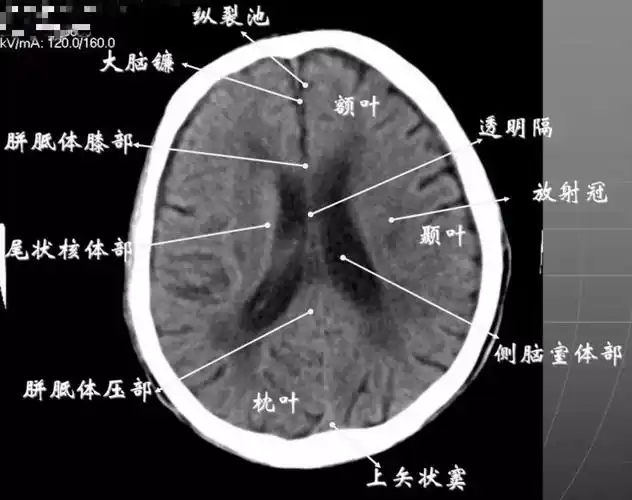

颅脑ct彩色解剖

读懂头颅ct并不难,教你成为读片小能手

全身ct图谱,赶紧收藏了吧